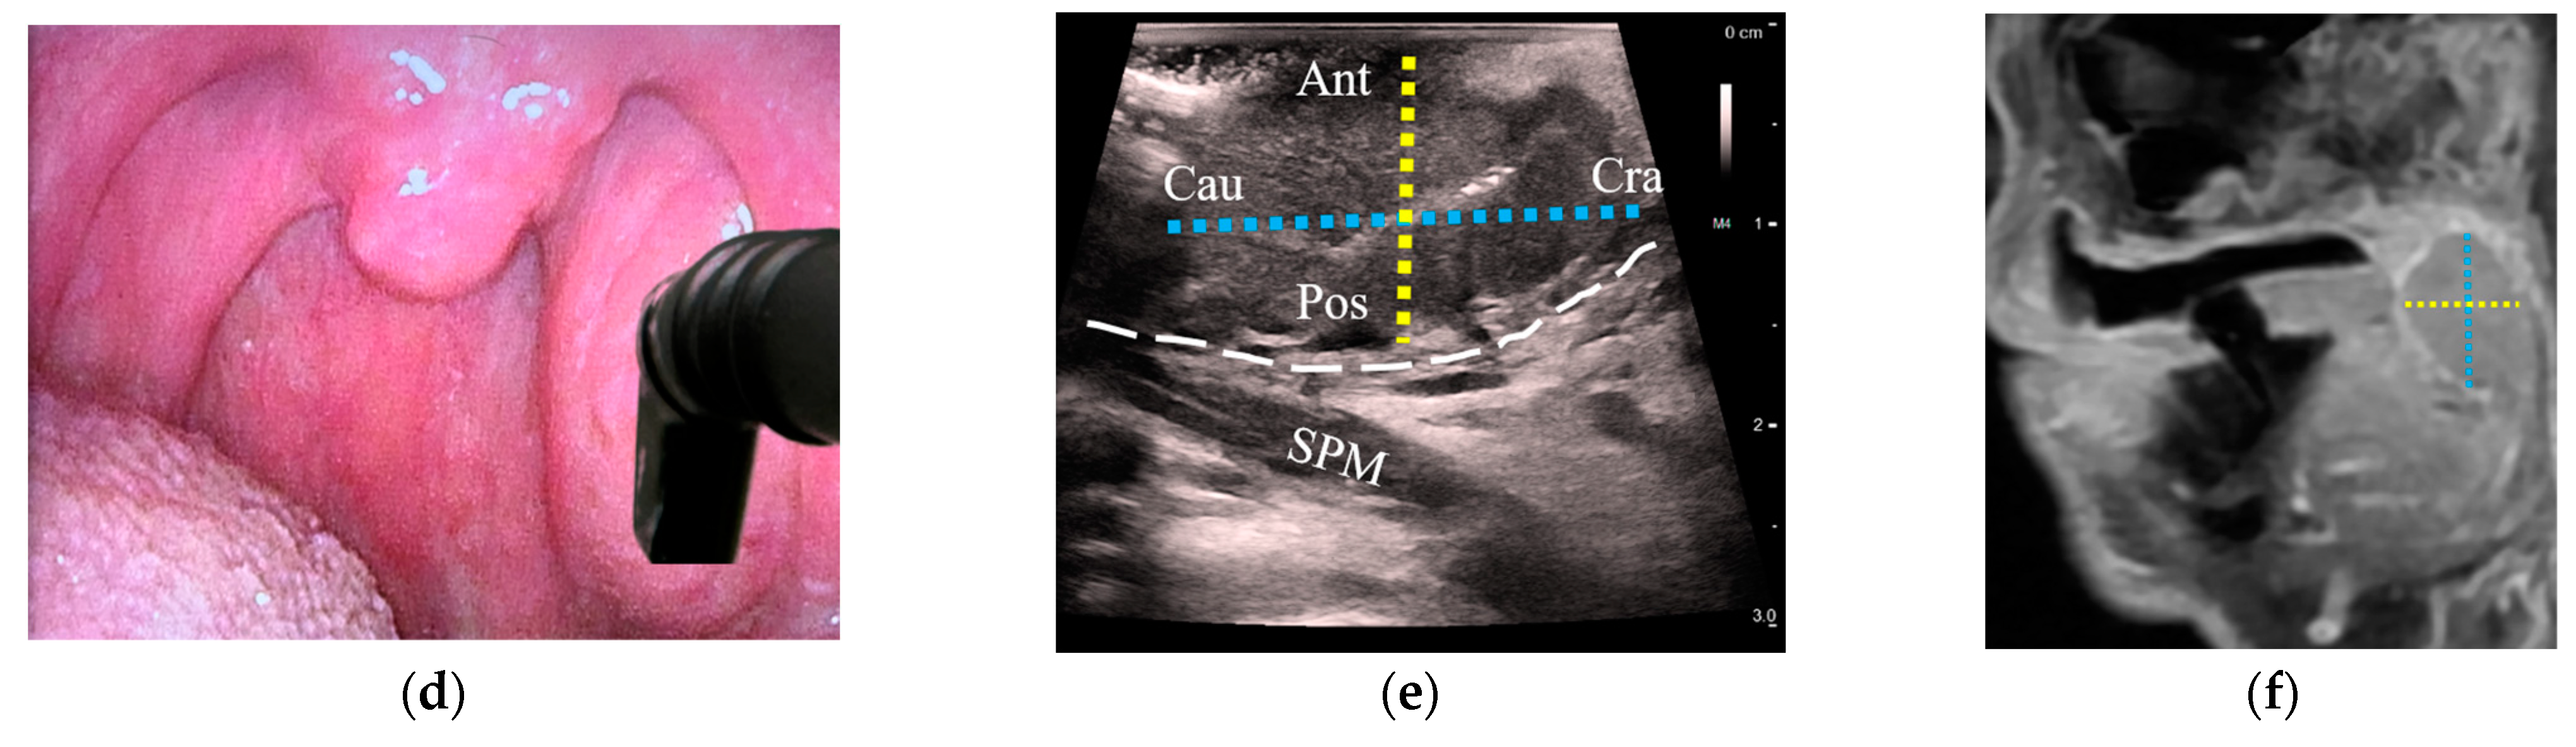

Figure 4.

Comparison of tumor diameters between transoral US and corresponding MRI images of a stage-T2 palatine tonsil HPV+ SCC: (a) a patient with an asymmetric left palatine tonsil with an inserted hockey-stick ultrasound transducer placed onto the tonsil in a transverse plane; (b) transverse US reveals a palatine tonsil tumor. Tumor diameters are represented from medial (Med) to lateral (Lat) with a red dotted line and from anterior (Ant) to posterior (Pos) with a yellow dotted line; (c) axial MRI with the corresponding diameters as in (b, red and yellow dotted lines); (d) transducer oriented in the sagittal plane; (e) sagittal US with the cranial (Cra) to caudal (Cau) diameter added (blue dotted line) along with Ant-Pos (yellow dotted line); (f) sagittal MRI with the corresponding diameters as in (e, blue and yellow dotted lines). US: ultrasound; MRI: magnetic resonance imaging; HPV+ SCC: human papillomavirus-positive squamous cell carcinoma; ICA: internal carotid artery; ECA: external carotid artery; MPM: medial pterygoid muscle; SPM: stylopharyngeus muscle; white dashed line: constrictor muscle; Ant: anterior; Pos: posterior; Med: medial; Lat: lateral; Cra: cranial; Cau: caudal.

Tumor size was estimated with both US and MRI in 18/21 patients with OPCs (86%); three patients whose tumors could not be delineated on US were excluded from analysis. In all cases, outpatient US was performed a median of 5 days after MRI (interquartile range: −2 to 10 days). A high correlation between US and MRI was observed when comparing the tumor diameter along the US depth axis, which corresponded to the anteroposterior diameter (R = 0.80, Figure 3a). The lateral US axes corresponding to craniocaudal (R = 0.54) and mediolateral diameters (R = 0.49) demonstrated moderate correlation with MRI (Figure 3b,c). Figure 4 illustrates transoral transducer orientations and the corresponding US axes compared to MRI.